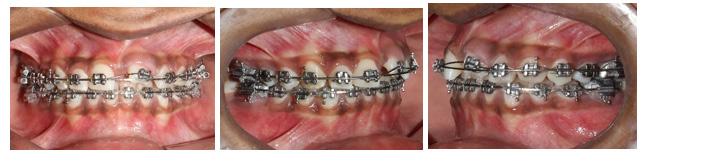

All selfies at T0 and T1 were cropped up to the clavicle of the subject if visible. The backgrounds of the selfies were removed and turned white with the help of Adobe Photoshop CC 2020 version 21.1 software package (Adobe Systems, San Jose, CA). One example of pre-treatment and post-treatment selfies of a subject in skeletal class I is illustrated in Figure 1A and 1B, in skeletal

Figure 1: Skeletal Class I Group (SCI) Male.

A-Pre-treatment (T0) Selfie; B- Post-treatment (T1) Selfie; C. Pretreatment Profile Silhouette (T0). D. Post-treatment Profile Silhouette

Figure 2: Skeletal Class II Group (SCII) Female.

A-Pre-treatment Selfie (T0), B- Post-treatment Selfie (T1). C. Pretreatment Profile Silhouette (T0), D. Post-treatment Profile Silhouette (T1).

Figure 3: Skeletal Class II Group (SCII) Female.

class II is illustrated in Figure 2A and 2B, and in skeletal class III is illustrated in Figures 3A and 3B.

All profile photographs at T0 and T1 were cropped up to the clavicle of the subject. Profile photographs were converted into black silhouettes against a white background using Adobe Photoshop CC 2020 version 21.1 software package (Adobe Systems, San Jose, CA) One example of pre-treatment and posttreatment profile silhouettes of a subject in skeletal class I is illustrated in Figure 1C and 1D, in skeletal class II is illustrated in Figure 2C and 2D, and in skeletal class III is illustrated in Figure 3C and 3D.